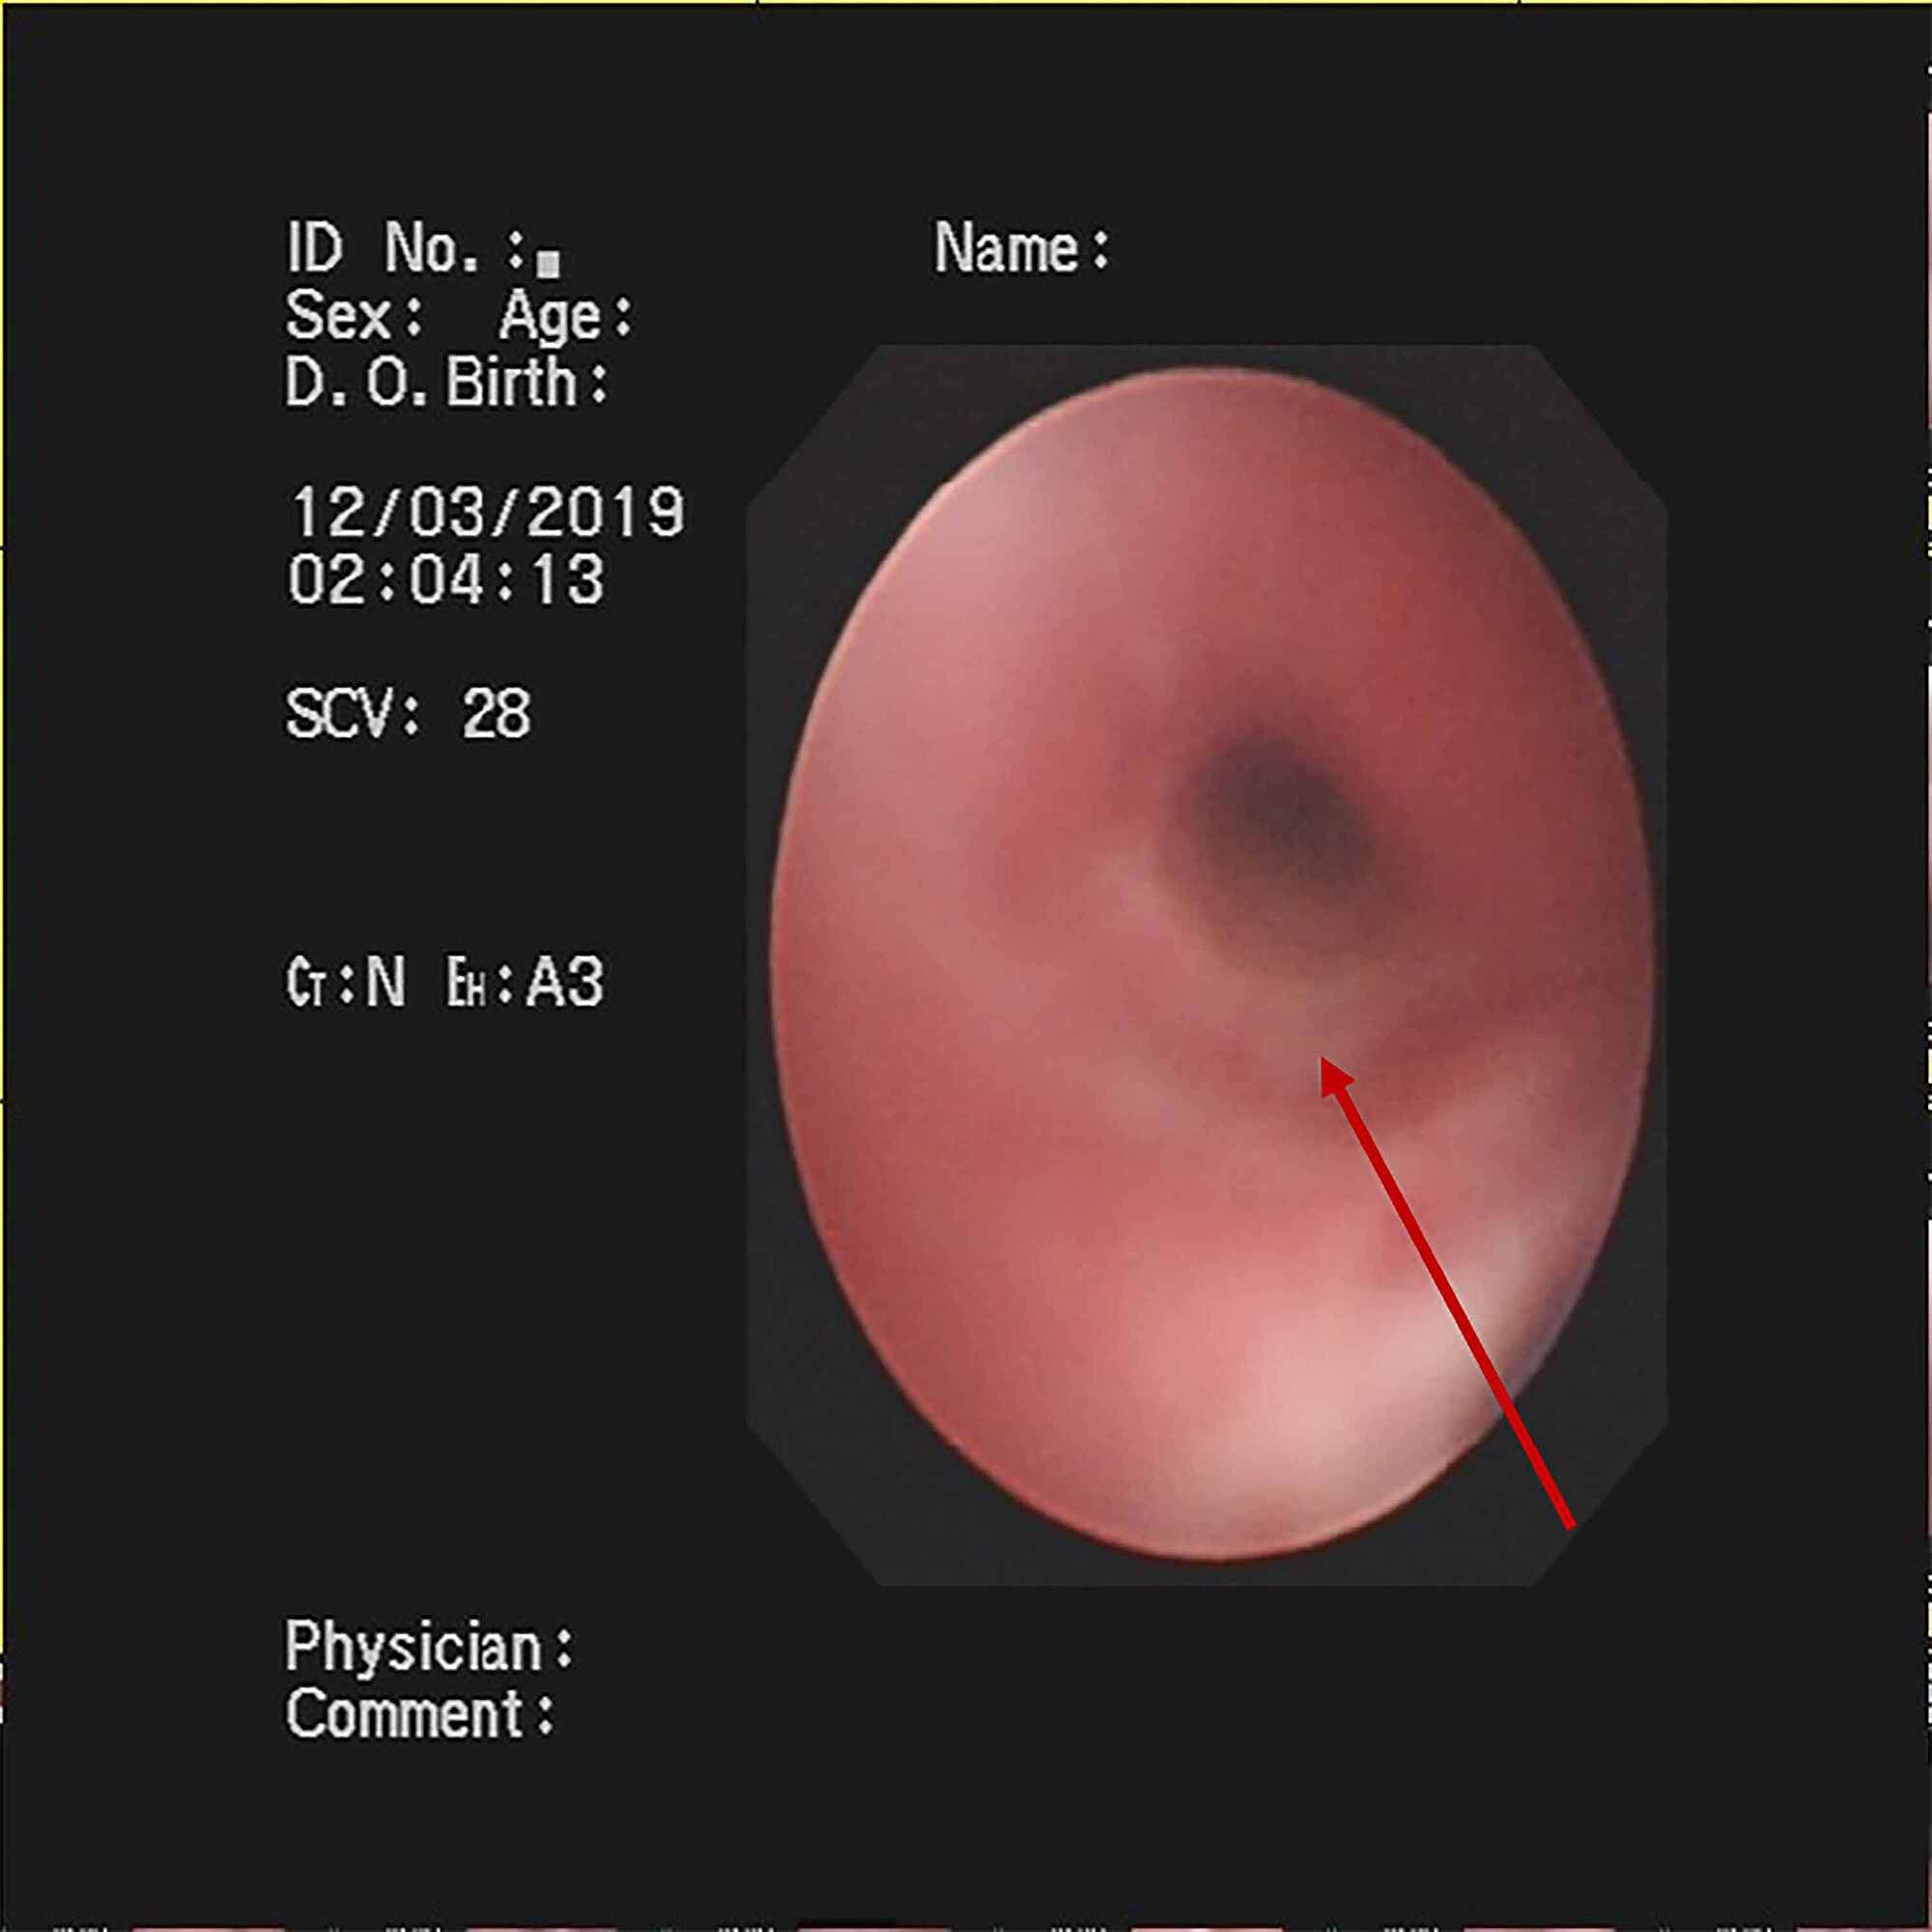

Treatment regimens were adjusted based on the etiological results. Imipenem-cilastatin sodium and vancomycin were discontinued; further, the patient was administered with piperacillin (50 mg/kg, bid), and added Oseltamivir for anti-influenza A virus. Azithromycin (10 mg/kg, qd), intravenous methylprednisolone (1 mg/kg, q12h), nebulized dexamethasone (5 mg, q6h), nebulized bronchodilators, intensive chest physiotherapy, and intravenous mucosolvan were continued. However, there was still no improvement. Considering the histopathology showed the casts predominantly comprised of mucin, and the mucolytic agent mucosolvan, as well as bronchodilators, were not effective, we used a mucolytic agent-α-chymotrypsin, which has been reported to liquefy the mucus. α-chymotrypsin (2000 IU, 5 mL saline) was intratracheally instilled twice a day via the endotracheal tube, supplemented by frequent intratracheal suction and chest physiotherapy. Consequently, abundant purulent secretions and casts were discharged (Figure 2B); further, the oxygen saturation increased to 93% and there were enhanced breath sounds in both lungs. The patient was successfully extubated with gradual improvement in his condition. Subsequently, the patient received oral azithromycin (10 mg/kg, three times per week) and nebulized budesonide (1 mg added in 2 mL saline, twice daily). Chest CT reexamination showed the full expansion of the left lung with pleural effusion on the left thorax and bilateral pneumonia (Figure 3A). Additionally, fiberoptic bronchoscopy revealed endobronchial intima infection without casts (Figure 4). After six days, he was discharged with a little cough and no neurological sequelae; continued on oral azithromycin and nebulized budesonide treatment for two weeks. The timeline of this case was shown in Figure 5. During the next four follow-up visits, the patient was asymptomatic and without recurrent casts. Further, his chest CT scan showed increased lung markings (Figure 3B).